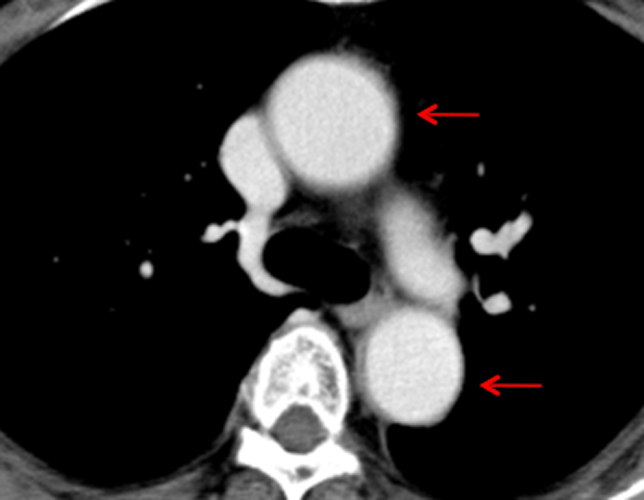

血管炎(高安動脈炎)

不明熱(原因が分からない長期間の発熱)の原因の一つに血管炎があります。血管炎はCTやMRIなどでは指摘が難しいことも多くあります。PET検査は全身の病変を一度に評価でき、活動性の把握にも役立ちます。

全身のMIP(最大値投映法)画像

大血管に一致した異常集積を広範囲に認めており、血管炎を反映した所見です。異常の範囲や活動性が一目瞭然です。

PETとCTの融合画像

血管への異常集積が明瞭です。

造影CT画像

血管の異常は認識が困難です。